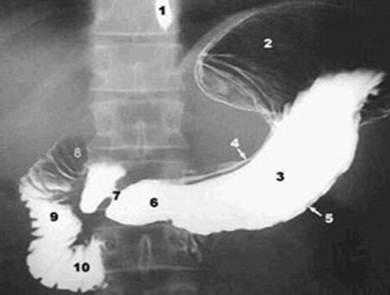

Рис. 9. Нормальная рентгенография (1 - пищевод, 2 - дно желудка, 3 - тело желудка, 4 - малая кривизна, 5 - большая кривизна, 6 - антральный отдел, 7 - привратник, 8 - луковица двенадцатиперстной кишки, 9 - нисходящая часть двенадцатиперстной кишки, 10 - горизонтальная часть двенадцатиперстной кишки)